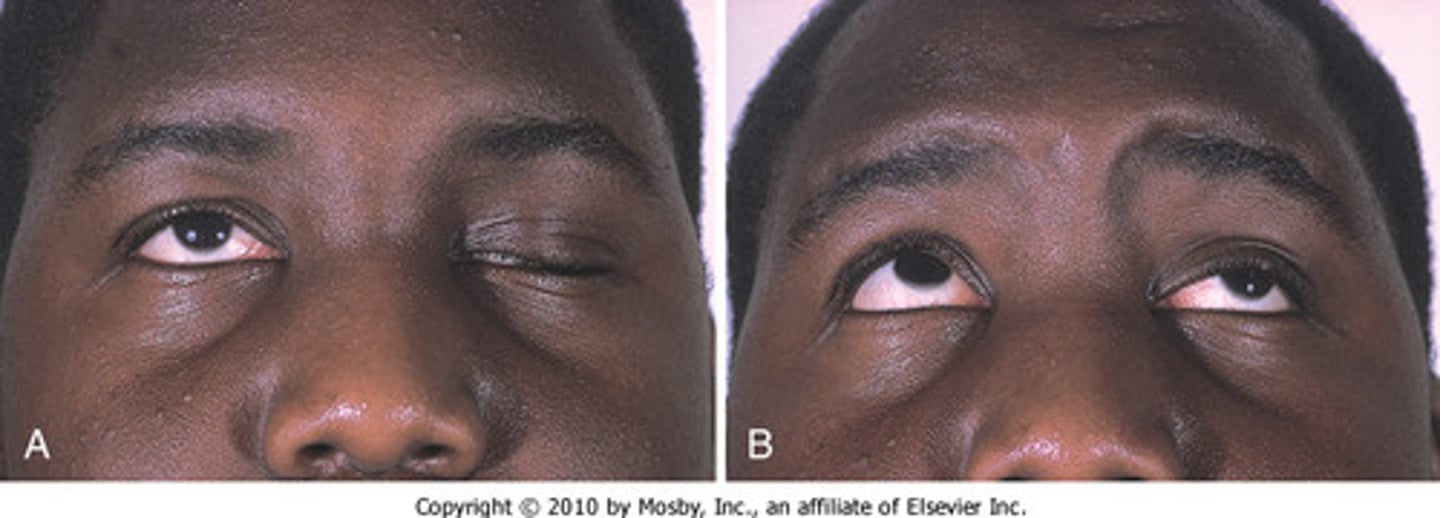

Myasthenia gravis

a chronic autoimmune disorder in which antibodies destroy the communication between nerves and muscle, resulting in weakness of the skeletal muscles